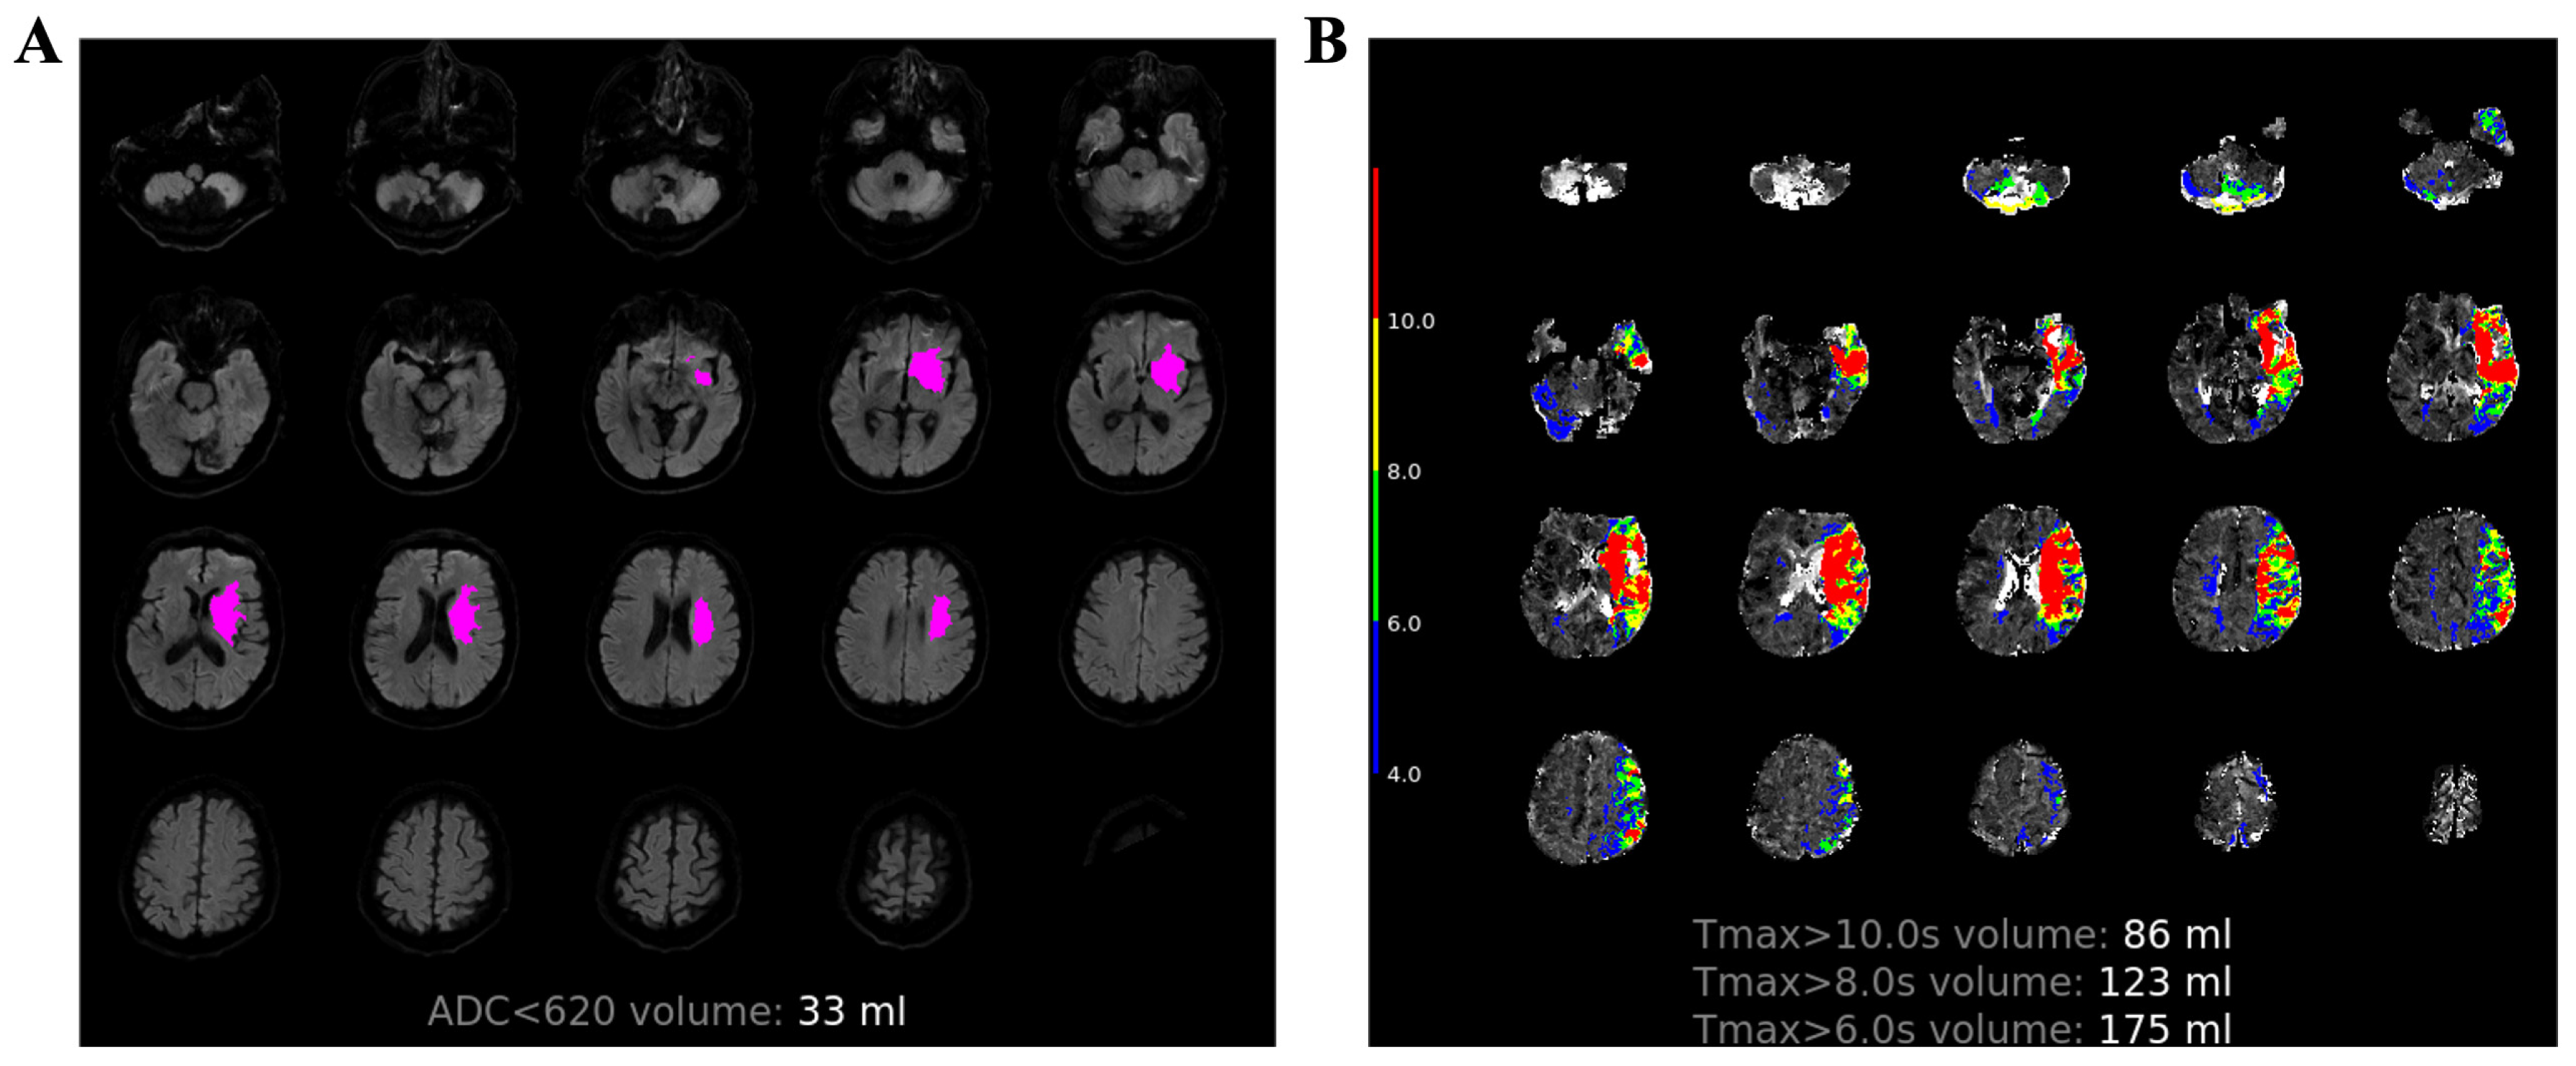

| ADC < 620 × 10−6 mm2/s (mL) | 5 (0–26.75) | 30 (8–91) | 0 (0–8) | <0.001 |

| Tmax > 6 s (mL) | 26.5 (0–123.75) | 141 (59–190) | 0 (0–37) | <0.001 |

| Tmax > 8 s (mL) | 7 (0–70.75) | 98 (33–137) | 0 (0–11) | <0.001 |

| Tmax > 10 s (mL) | 3 (0–40.5) | 71 (23–102) | 0 (0–4.5) | <0.001 |